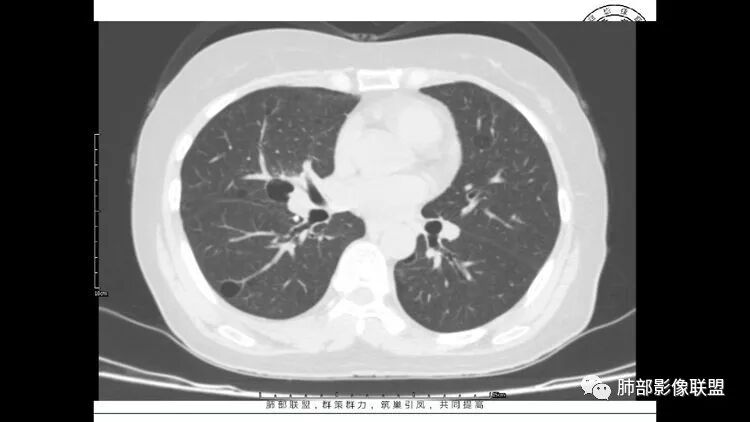

患者中年女性,因右眼红痛1天就诊。胸CT:双肺多发囊性变及结节影,囊以中下肺为多,部分囊内可见分隔及肺动脉,结节部分为实性,部分为混合性,边缘光滑,未见明显毛刺、棘突、胸膜牵拉及血管集束征象。双中下可见支气管扩张及树丫征。淋巴结无明显肿大。综合考虑:一元淋巴细胞间质性肺炎。多元鉴别肺腺癌并转移等恶性病变。

中年女性,因“角膜炎”入院,自用眼液2年,(眼干?)肺部:双肺多发类圆形薄壁气囊+实性结节+GGO,下肺分布为主,纵隔淋巴结肿大,考虑淋巴系统增殖,LIP可能性大,可能继发于干燥综合症;左肺下叶的混合磨玻璃结节形迹可疑,边界清晰,内部疑似空泡,扩张扭曲支气管,极像肺癌,伴双肺转移?待排吧

wonderful

多发气囊,气囊内可见血管进入,因患者眼干伴类风湿,可能有干燥综合征,那LIP可能性大。因为不是育龄期发病,可排除LAM。患者左纵膈淋巴结肿大,且有融合趋势,结合左下肺病灶,考虑合并恶性肿瘤,淋巴瘤?鉴别结节病